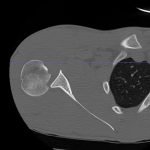

Radiographs demonstrated posterior displacement of the humeral head on the “Y” view (see white arrow) and widening of the glenohumeral joint space on anterior-posterior view (see red arrow). The findings were consistent with posterior dislocation and a Hill-Sachs type deformity.  Sedation was performed and reduction was attempted using external rotation, traction counter-traction. An immediate “pop” was felt during the procedure. Post-procedure radiographs revealed a persistent posterior subluxation with interlocking at posterior glenoid. CT revealed posterior dislocation with acute depressed impaction deformity medial to the biceps groove with the humeral head perched on the posterior glenoid, interlocked at reverse Hill-Sachs deformity (see blue arrow).